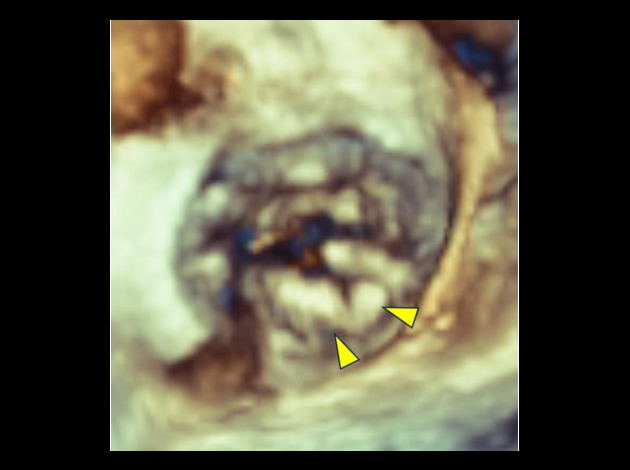

心臓腫瘍(左房粘液腫)